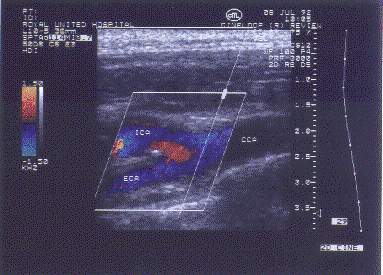

Existem diferentes técnicas de ultra-sonografia, valendo ser lembradas aqui a ecografia B, o eco-doppler colorido e a ecografia tridimensional. A ecografia B (brilho) é realizada com transdutor manual, registrando os ecos recebidos na forma de variados graus de brilho superpostos, com fundo escuro por consenso, sendo possível inverter este padrão de imagem. O eco-doppler colorido é bastante útil no estudo vascular, constituindo um método não-invasivo que permite avaliação da parede vascular, do fluxo e do débito. Por convenção, o fluxo que se aproxima do transdutor é vermelho e o que se afasta é azul. A ecografia tridimensional promete ser o grande método ultra-sonográfico no futuro, estando ainda muito incipiente.

Fig. 2 - Doppler colorido mostrando bifurcação da artéria carótida comum em carótidas externa e interna